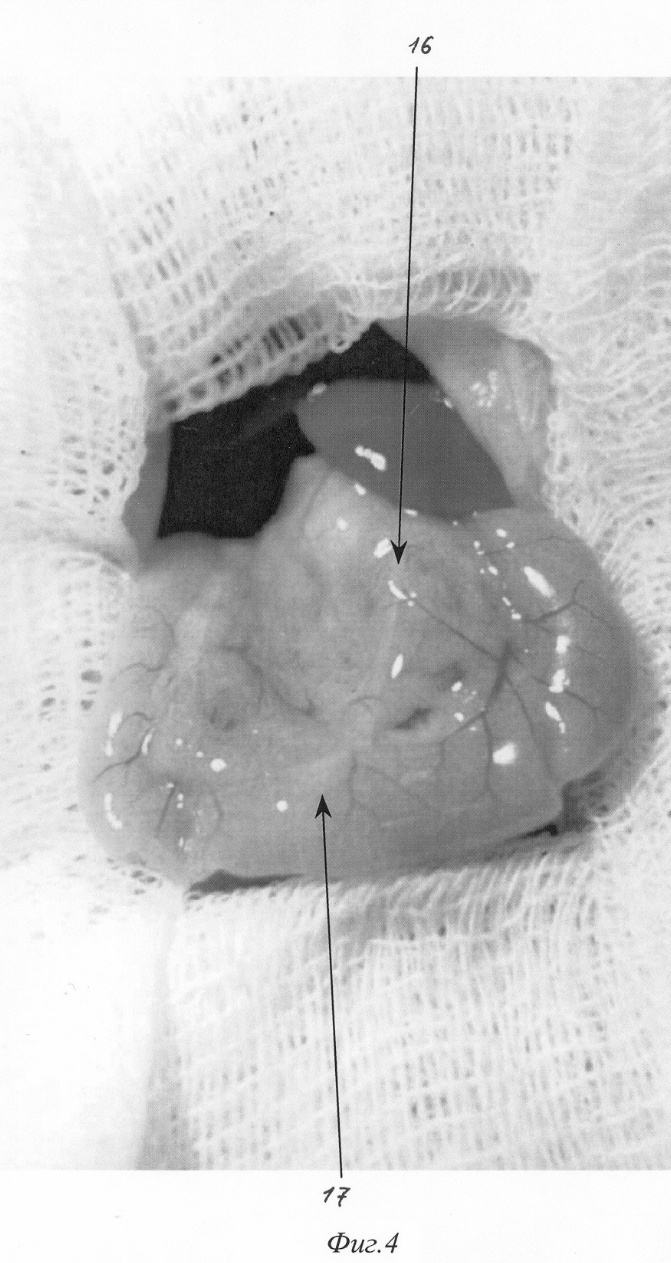

Изобретение относится к медицине, а именно к экспериментальной хирургии, и может быть использовано для моделирования острого деструктивного панкреатита у крыс. Близким решением является способ моделирования, разработанный Aho HJ, Koskensalo SM, и Nevalainen TJ, описанный в статье Experimental pancreatitis in the rat. Sodium taurocholate-induced acute haemorrhagic pancreatitis. Scand J Gastroenterol 15: 411-416, 1980. Который заключается в трансдуоденальной катетеризации общего желчного протока и введение таурохолата натрия (0,4 мл 4% раствора) в общий желчный проток и протоки поджелудочной железы. При использовании данного способа моделирования острого деструктивного панкреатита патогенетические механизмы, лежащие в основе большого количества летальных исходов, отличаются от таковых при развитии острого панкреатита в клинике. Так, таурохолат, являясь гемолитическим ядом, при применении в вышеуказанных концентрациях вызывает внутрисосудистый гемолиз. Другим отрицательным свойством данной модели является невозможность влияния на площадь панкреонекроза. Немаловажным фактором, влияющим на интрапанкреатическую активацию ферментов поджелудочной железы, является уровень рН в ее протоковой системе, что никак не учитывается в данной модели. Задачей изобретения является разработка модели острого панкреатита, наиболее оптимально соответствующей патогенетическим механизмам, имеющим место при развитии острого панкреатита у человека, позволяющей регулировать площадь панкреонекроза, а также снижение летальности, обусловленной гемолитическим действием вводимого в протоки раствора. Поставленная задача решаются тем, что для моделирования острого деструктивного панкреатита вместо раствора таурохолата натрия мы используем трансдуоденальное внутрипротоковое введение специальной буферной системы, содержащей соль желчной кислоты при оптимальной для интрапанкреатической активации ферментов рН. Для возможности управления площадью панкреонекроза мы используем различное наложение (дистальнее или проксимальнее места впадения добавочного протока поджелудочной железы в общий желчный проток) лигатуры, что обеспечивает развитие тотального или субтотального панкреонекроза. Изобретение поясняется фигурами: – на фиг.1 изображено строение протоковой системы крысы (1); – на фиг.2 изображено строение протоковой системы крысы (2); – на фиг.3 изображен первый этап моделирования (срединная лапаротомия); – на фиг.4 изображен второй этап моделирования (выведение органов в рану); – на фиг.5 изображен третий этап моделирования (пункция двенадцатиперстной кишки и катетеризация общего желчного протока); – на фиг.6 изображен пример наложения турникетов для воспроизведения субтотального панкреонекроза; – на фиг.7 изображен пример наложения турникетов для воспроизведения тотального панкреонекроза; – на фиг.8 изображен пятый этап моделирования – ушивание лапаротомной раны. Способ осуществляется следующим образом. Операция проводится с соблюдением правил асептики и антисептики под эфирным наркозом. После обработки операционного поля послойно вскрывается брюшная полость (верхнесрединная лапаротомия) на протяжении 2-3 см (фиг.3). Операционное поле отгораживается стерильными салфетками. При вскрытии брюшной полости в рану выводится петля двенадцатиперстной кишки (фиг.2. 12, фиг 4). В гепатодуоденальной связке определяется общий желчный проток крысы диаметром 0,3-0,5 мм (фиг.2. 11, фиг.4. 16 ). На расстоянии приблизительно 1,5 см от ворот печени (фиг.2. 10) в общий желчный проток по задней поверхности впадает главный панкреатический проток (фиг.2. 9), который собирает секрет от желудочной и селезеночной частей поджелудочной железы и имеет диаметр приблизительно около 0,2-0,3 мм, что лучше видно при рассечении связки аналоги lig. gastrocolicum и отведении желудка кверху (фиг.1). При этом мы увидим дистальную часть общего желчного протока (фиг.1. 2), впадающий в него главный панкреатический проток (фиг.1. 3), желудочную часть поджелудочной железы (фиг.1. 7), прилежащую к задней стенке желудка (фиг.1. 4), и селезеночную часть поджелудочной железы (фиг.1. 6), прилежащую к воротам селезенки (фиг.1. 5). Также при этом доступе можно увидеть и дуоденальную часть поджелудочной железы (фиг.1. 8), дренирующуюся дополнительным протоком (фиг.1. 1), который впадает в общий желчный проток по задней его поверхности на расстоянии около 0,5 см от места вхождения общего желчного протока в стенку двенадцатиперстной кишки. Место впадения дополнительного панкреатического протока в общий желчный проток можно увидеть и при выведении ДПК, как это показано на фиг.2. 19. Интрамуральный отдел общего желчного протока (фиг.2. 14) открывается в просвет ДПК, что можно увидеть через стенку кишки (фиг.2. 14, фиг.4. 17). Найдя место впадения общего желчного протока от него отступают около 0,5 см в этом месте производят пункцию двенадцатиперстной кишки зондом, диаметром 0,3 мм (фиг.5. 19), который через большой дуоденальный сосочек проводится в общий желчный проток до середины расстояния между местами впадения панкреатических протоков (фиг.5. 19). После этого на общий желчный проток накладывается два турникета. Один выше места впадения основного панкреатического протока (фиг.6. 20, фиг.7. 22), второй, в зависимости от того, какую форму панкреатита необходимо воспроизвести (тотальную или субтотальную), выше (фиг.6. 21) или ниже (фиг.7. 23) места впадения добавочного протока поджелудочной железы. Турникеты затягивают. В проток при помощи насоса для микроинфузий вводят 0,3 мл буфера (содержащего 0,3 г трис-гидроксиметил-аминометана и 0,6 г дезоксихолата натрия в 100 мл при рН 8,8) при скорости потока 0,07 мл в минуту. Турникеты с протоков снимают спустя минуту после прекращения введения буфера и удаляют катетер из протока. После создания модели органы погружаются в брюшную полость. Убираются отгораживающие салфетки. Брюшная полость послойно ушивается отдельными шелковыми швами (фиг.8). Рана обрабатывается раствором антисептика. Пример конкретного применения. Исследование проведено на 100 самках крыс линии Вистар массой 200 г. С целью подтверждения наличия острого деструктивного панкреатита производилось морфологическое исследование образцов поджелудочной железы на сроке 12 часов (как наиболее информативного срока). Образцы поджелудочной железы забирались, фиксировались в 10% растворе нормального формалина, обезвоживались, заливались в парафин, готовились парафиновые срезы, которые затем окрашивались гематоксилин-эозином. Также производилось исследование активности амилазы в сыворотке крови и перитонеальном экссудате амилокластическим методом со стойким крахмальным субстратом по Каравею. Кроме этого оценивалась летальность за первые сутки с момента моделирования. Полученные данные сравнивали с данным контрольной группы (интактные животные). Так, нормальные значения активности амилазы, вычисленные для нашей лаборатории, – 61,76 г/ч/л. После моделирования острого панкреатита описанным выше методом через 12 часов с момента моделирования активность амилазы сыворотки крови при тотальном панкреонекрозе достигает уровня 144,77±3,2 г/ч/л (р<0,01), а перитонеального экссудата 1237,36±7,4 г/ч/л (р<0,01) г/ч/л, при субтотальном панкреонекрозе 160,56±4,3 г/ч/л (р<0,01) и 1548,21±8,3 г/ч/л (р<0,01) – соответственно. При морфологическом исследовании получены следующие результаты: Макроскопическая картина при вскрытии брюшной полости и грудной клетки крысы после моделирования тотального панкреонекроза. При вскрытии в брюшной полости до 5 мл серозно-геморрагического выпота во всех отделах, гиперемия париетальной и висцеральной брюшины брыжейка тонкой кишки отечна, с множественными мелкими очагами стеатонекроза. Печень не увеличена, темно-вишневого цвета, поверхность ее гладкая, края долей заострены. Почки без видимой макроскопической патологии. Селезенка умеренно увеличена в размерах, темно-вишневого цвета. При вскрытии просвета желудка и ДПК определяются множественные мелкие (точечные) эрозии шоколадного цвета. Поджелудочная железа резко отечна с участками стеатонекроза размерами от 0,3 до 0,5 см в диаметре. В области желудочно-дуоденальной части имеются участки геморрагического панкреонекроза размерами до 0,3 см в диаметре. Отмечается отек забрюшинной клетчатки. При вскрытии грудной клетки определяется гиперемия плевры и небольшое количества светлого выпота. Поверхность легких гладкая, буроватого цвета с множественными точечными кровоизлияниями. Сердце без видимых макроскопических изменений. Морфологическое исследование поджелудочной железы (окраска гематоксилин-эозином увеличение 20 В дуоденальной части определяется зона тотального некроза с участками геморрагии, массивной нейтрофильно-макрофагальной инфильтрацией. Структура ацинусов не сохранена. В желудочной части имеет место крупноочаговый панкреонекроз с единичными участками геморрагии, клеточными структурами разрушенных панкреатоцитов, нейтрофильно-макрофагальной инфильтрацией. В зонах, удаленных от очагов некроза, структура ацинусов сохранена. В участках, примыкающих к зонам некроза, панкреатоциты имеют вакуолизированную цитоплазму, ядра неправильной формы. В селезеночной части определяются множественные центролобулярные некрозы. Имеется значительное количество ацинусов с сохраненной структурой, встречаются интактные островки Лангерганса. Макроскопическая картина при вскрытии брюшной полости и грудной клетки крысы после моделирования субтотального панкреонекроза. При вскрытии брюшной полости определяется до 3-4 мл серозно-геморрагического выпота. Париетальная и висцеральная брюшина гиперемирована во всех отделах. Брыжейка тонкой кишки отечна, с умеренным количеством мелких очагов стеатонекроза. Печень не увеличена, темно-вишневого цвета, поверхность ее гладкая, края долей заострены. На разрезе структура паренхемы не изменена, сосуды полнокровны. Селезенка умеренно увеличена в размерах, темно-вишневого цвета. Почки увеличены серовато-бурого цвета, на разрезе отчетливо просматривается кортикальный слой, темно-вишневого цвета с серым оттенком. При вскрытии просвета желудка и ДПК определяются множественные мелкие эрозии шоколадного цвета. Поджелудочная железа резко отечна с участками стеато и геморрагического панкреонекроза в желудочной части до 0,3 см в диаметре и участками стеатонекроза в парапанкреатической клетчатке. Дуоденальная часть железы отечна. При вскрытии грудной клетки определяется гиперемия плевры и небольшое количества светлого выпота. Поверхность легких гладкая, буроватого цвета с множественными точечными кровоизлияниями. Сердце без видимых макроскопических изменений. Морфологическое исследование поджелудочной железы (окраска гематоксилин-эозином увеличение 20 В дуоденальной части определяется интерстициальный отек с геморрагическим пропитыванием. Структура ацинусов сохранена. В желудочной части имеет место крупноочаговый панкреонекроз с единичными участками геморрагий, клеточными структурами разрушенных панкреатоцитов, нейтрофильно-макрофагальной инфильтрацией. В зонах, удаленных от очагов некроза, структура ацинусов сохранена. В участках, примыкающих к зонам некроза, панкреатоциты имеют вакуолизированную цитоплазму, ядра неправильной формы. В селезеночной части определяются множественные центролобулярные некрозы. Имеется значительное количество ацинусов с сохраненной структурой, встречаются интактные островки Лангерганса. При моделировании острого панкреатита летальность к первым суткам составила 80,6% при тотальном панкреонекрозе и 56,3% при субтотальном панкреонекрозе. В образцах крови, взятых при тотальном и при субтотальном панкреонекрозе, гемолиза не выявлено. Таким образом, поставленная задача достигнута, во первых, за счет уменьшения количества желчной кислоты в водимом в протоки растворе, во вторых, за счет поддержания рН вводимого раствора на оптимальном для активации ферментов уровне, в третьих, за счет наложения турникета до или после места впадения дополнительного протока поджелудочной железы в общий желчный проток и управления площадью некроза. В результате применения данного способа моделирования острого панкреатита развивается крупноочаговый некроз поджелудочной железы (тотальный или субтотальный), что, в свою очередь, приводит к: 1. Выявлению достоверных признаков развития острого панкреатита (морфологических и биохимических). 2. Возможности управления площадью некроза. 3. Снижению уровня летальности, связанной с гемолитическим действием солей желчных кислот. Формула изобретения